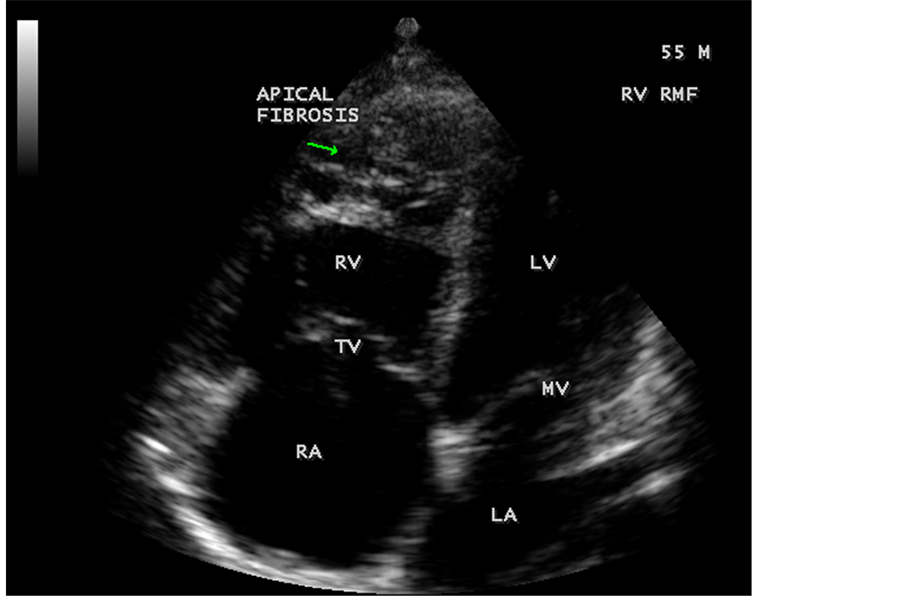

pressure 100/70 mmHg. Auscultation revealed diminished breath sounds on the right side of the chest with a dull note on percussion and a loud P2 (pulmonic component of second heart sound) with grade 2/6 soft systolic murmur over the lower left sternal border which increases in intensity with deep inspiration (Carvallo’s sign) suggesting tricuspid regurgitation. ECG revealed no arrhythmias and X-ray chest showed right- sided pleural effusion and extensive calcification over the cardiac shadow as shown in Figure 9. Transthoracic echocardiography revealed apical fibrosis of right ventricle, moderate pericardial effusion, right atrial dilatation as shown in Figure 10 and Figure 12, suggesting right ventricular endomyocardial fibrosis and severe tricuspid regurgitation as in Figure 11, Figure 13 and Figure 14 indicates coexisting pulmonary hypertension due to pulmonary damage caused by tuberculosis as shown in Figure 13 and free RV outflow tract as in Figure 15. Patient was treated with antituberculous drugs, antifailure measures such as digoxin and diuretics, ascites fluid tapping and antibiotics. He showed mild improvement in his symptoms.

Figure 11. Apical four chamber view suggesting RV (right ventricular) apical fibrosis, RA dilatation and severe tricuspid regurgitation suggesting right ventricular endomyocardial fibrosis with an extension of fibrosis in the LV apex.

Figure 12. Apical four chamber view showing the RV apical fibrosis with mild pericardial effusion in a 23-year-old male with tuberculosis.

Figure 83. Classical RV EMF with apical fibrosis in a 55-year-old male.

Figure 84. Classical RV EMF with apical fibrosis and tricuspid regurgitation in a 55-year-old male.